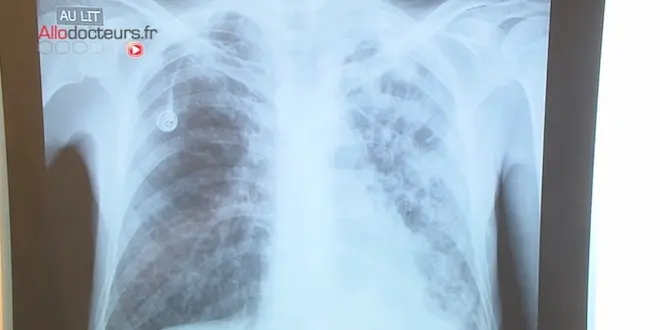

"La tuberculose responsable de ce décès n’a pu être détectée avant le décès de l'enfant. En effet, pendant toute la durée de sa prise en charge, ses examens de thorax et prélèvements bronchiques s'étaient révélés normaux", a précisé l’agence par voie de communiqué.

La tuberculose est une maladie contagieuse qui se transmet par voie aérienne (toux, éternuement, etc.). Elle se manifeste par la persistance de certains symptômes pulmonaires (toux, difficultés ou douleurs respiratoires, crachats...) ou généraux (fièvres, sueurs nocturnes, amaigrissement anormal...). La tuberculose se soigne aisément avec des antibiotiques adaptés.